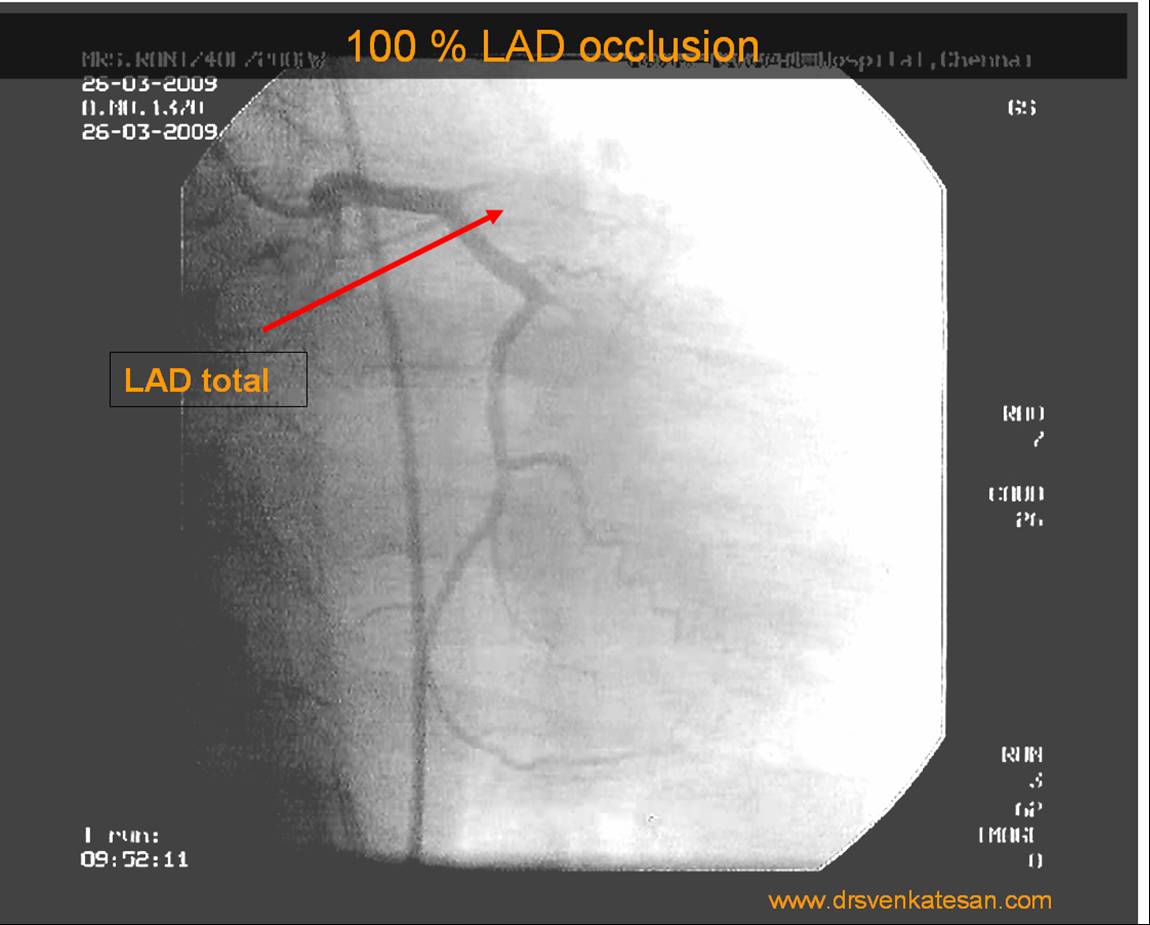

Reassurance is a revascularization equivalent

Sharing a similar experience with one of my patients in his early fifties. After getting a fairly convincing consultation, he accepted medical management. However, guided by both NI & AI, he sought a second opinion to confirm whether my assurance was indeed correct. He underwent FFR and OCT, and both he and his plaque became vulnerable. The FFR was normal. He was too intelligent to ask about the FFR – Stress test discordance, for which his cardiologist had no answer. Still, they did not advise a PCI and the decision was left to him, respecting the current patient-oriented guidelines.

The patient went home empowered but spent sleepless nights, fearing about potential fissures, in the life sustaining fibrous cap.He believed that he was at the mercy of a 75-micron thin cap covering his plaque. In one of the anxious days,in the following week , he got admitted himself in a posh downtown cardiac center. A as per the guidelines, the patient chose his own pathway for a PCI. Cardiologists obliged piously to his wishes. Now, he feels better. He says he is happy to undergo a self prescribed stent.